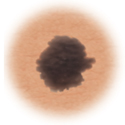

| Moles (nevi) |

Small skin marks caused by pigment-producing cells in the skin. Moles can be flat or raised, smooth or rough, and some contain hair. Most moles are dark brown or black, but some are skin-colored or yellowish. Moles can change over time and often respond to hormonal changes. |

Most moles are benign and no treatment is needed. Some benign moles may develop into skin cancer (melanoma). See below for signs. |

| Atypical moles (dysplastic nevi) |

Larger than normal moles (more than a half inch across), atypical moles are not always round. Atypical moles can be tan to dark brown, on a pink background. These types of moles may occur anywhere on the body. |

Treatment may include removal of any atypical mole that changes in color, shape, or diameter. In addition, people with atypical moles should avoid sun exposure, since sunlight may accelerate changes in atypical moles. People with atypical moles should see a healthcare provider for any changes that may indicate skin cancer. |

Distinguishing benign moles from melanoma

Certain moles are at higher risk of changing into malignant melanoma, a form of skin cancer. Large moles that are present at birth and atypical moles have a greater chance of becoming cancerous. Finding cancerous skin growths early is important because that’s when treatment is most likely to be effective. Removing the melanoma through surgery seems to work best as the treatment. When a melanoma is diagnosed early, surgery usually removes all the cancer.

Use this ABCDE chart below to help you see changes in your moles at the earliest stages. The warning signs include: